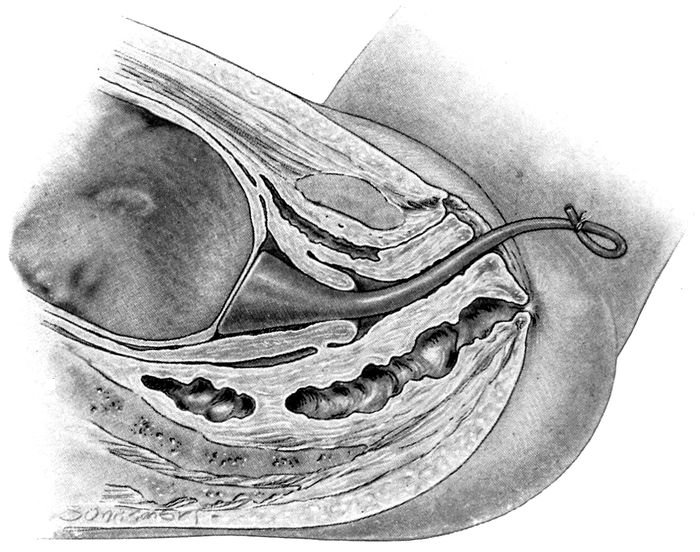

| 80. |

190 |

| 81. |

191 |

| 82. |

192 |